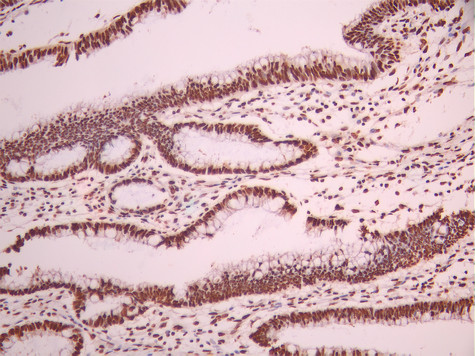

IHC image of CSB-RA982352A0HU diluted at 1:100 and staining in paraffin-embedded human gastric cancer performed on a Leica BondTM system. After dewaxing and hydration, antigen retrieval was mediated by high pressure in a citrate buffer (pH 6.0). Section was blocked with 10% normal goat serum 30min at RT. Then primary antibody (1% BSA) was incubated at 4°C overnight. The primary is detected by a Goat anti-rabbit polymer IgG labeled by HRP and visualized using 0.05% DAB.